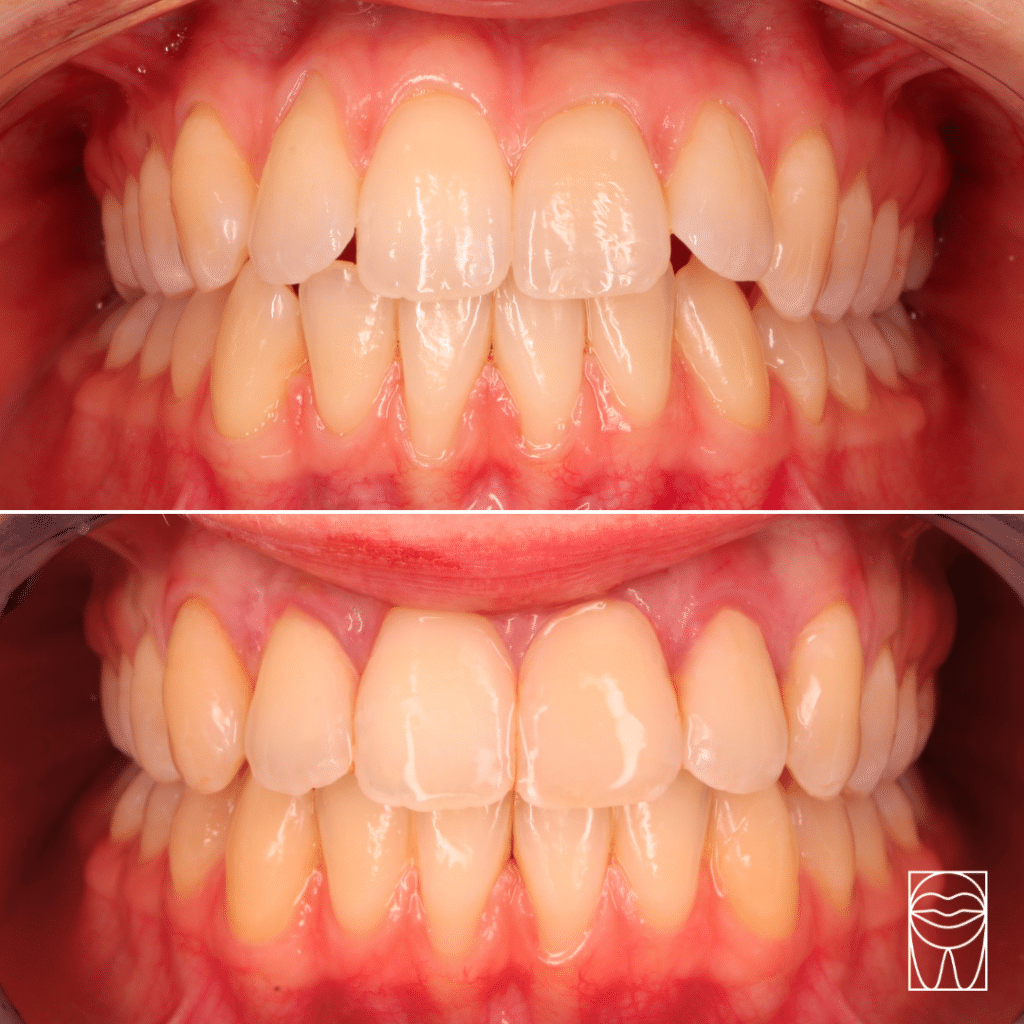

Inversé

d'articulé

Malocclusion

L’inversé d’articulation : situation où les dents de devant et de l’arcade supérieure sont inversées par rapport au dents de devant et de l’arcade inférieure.

Classe

II

Malocclusion

La classe II : l’arcade supérieure est trop avancée par rapport à l’arcade inférieure. Les raisons peuvent être d’ordre dentaire ou squelettique.

Classe

III

Malocclusion

La classe III : contrairement à la classe II l’’arcade inférieure est ici trop avancée par rapport à l’arcade supérieure. Là encore, les raisons sont liées à la dentition ou au squelette.

Nos résultats